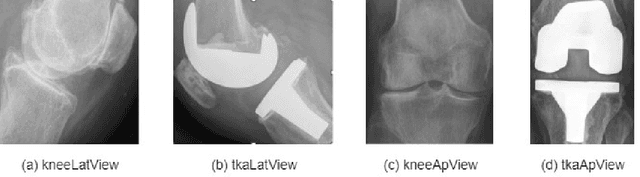

Abstract:Knee pain is undoubtedly the most common musculoskeletal symptom that impairs quality of life, confines mobility and functionality across all ages. Knee pain is clinically evaluated by routine radiographs, where the widespread adoption of radiographic images and their availability at low cost, make them the principle component in the assessment of knee pain and knee pathologies, such as arthritis, trauma, and sport injuries. However, interpretation of the knee radiographs is still highly subjective, and overlapping structures within the radiographs and the large volume of images needing to be analyzed on a daily basis, make interpretation challenging for both naive and experienced practitioners. There is thus a need to implement an artificial intelligence strategy to objectively and automatically interpret knee radiographs, facilitating triage of abnormal radiographs in a timely fashion. The current work proposes an accurate and effective pipeline for autonomous detection, localization, and classification of knee joint area in plain radiographs combining the You Only Look Once (YOLO v3) deep convolutional neural network with a large and fully-annotated knee radiographs dataset. The present work is expected to stimulate more interest from the deep learning computer vision community to this pragmatic and clinical application.